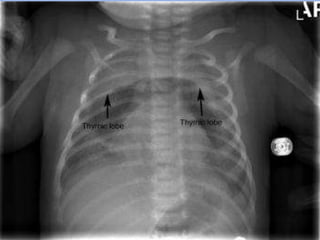

SPINNAKER SIGN

The spinnaker sign (the angel wing sign) is a sign of pneumomediastinum seen on

neonatal chest radiographs.

It refers to the thymus being outlined by air with each lobe displaced laterally and

appearing like spinnaker sails.

SPINNAKER SIGN The spinnakersign (the angel wing sign) is a sign of pneumomediastinum seen on neonatal chest radiographs. It refers to the thymus being outlined by air with each lobe displaced laterally and appearing like spinnaker sails.